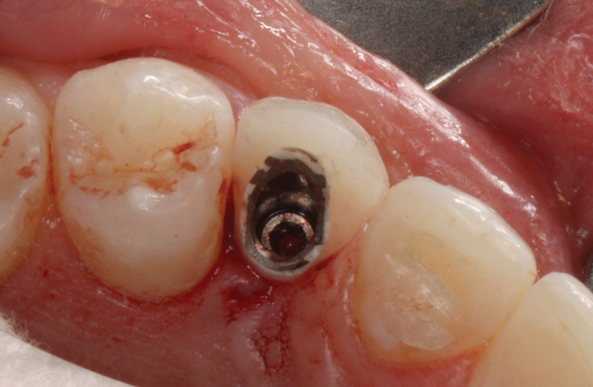

(35.) An implant being inserted into the prepared osteotomy of a patient who presented for the replacement of the maxillary left central incisor.

Figure 35

(36.) The implant’s primary stability was assessed by RFA, and the ISQ value greater than 65 was used to determine that immediate provisionalization was indicated.

Figure 36

(37.) The implant’s primary stability was assessed by RFA, and the ISQ value greater than 65 was used to determine that immediate provisionalization was indicated.

Figure 37